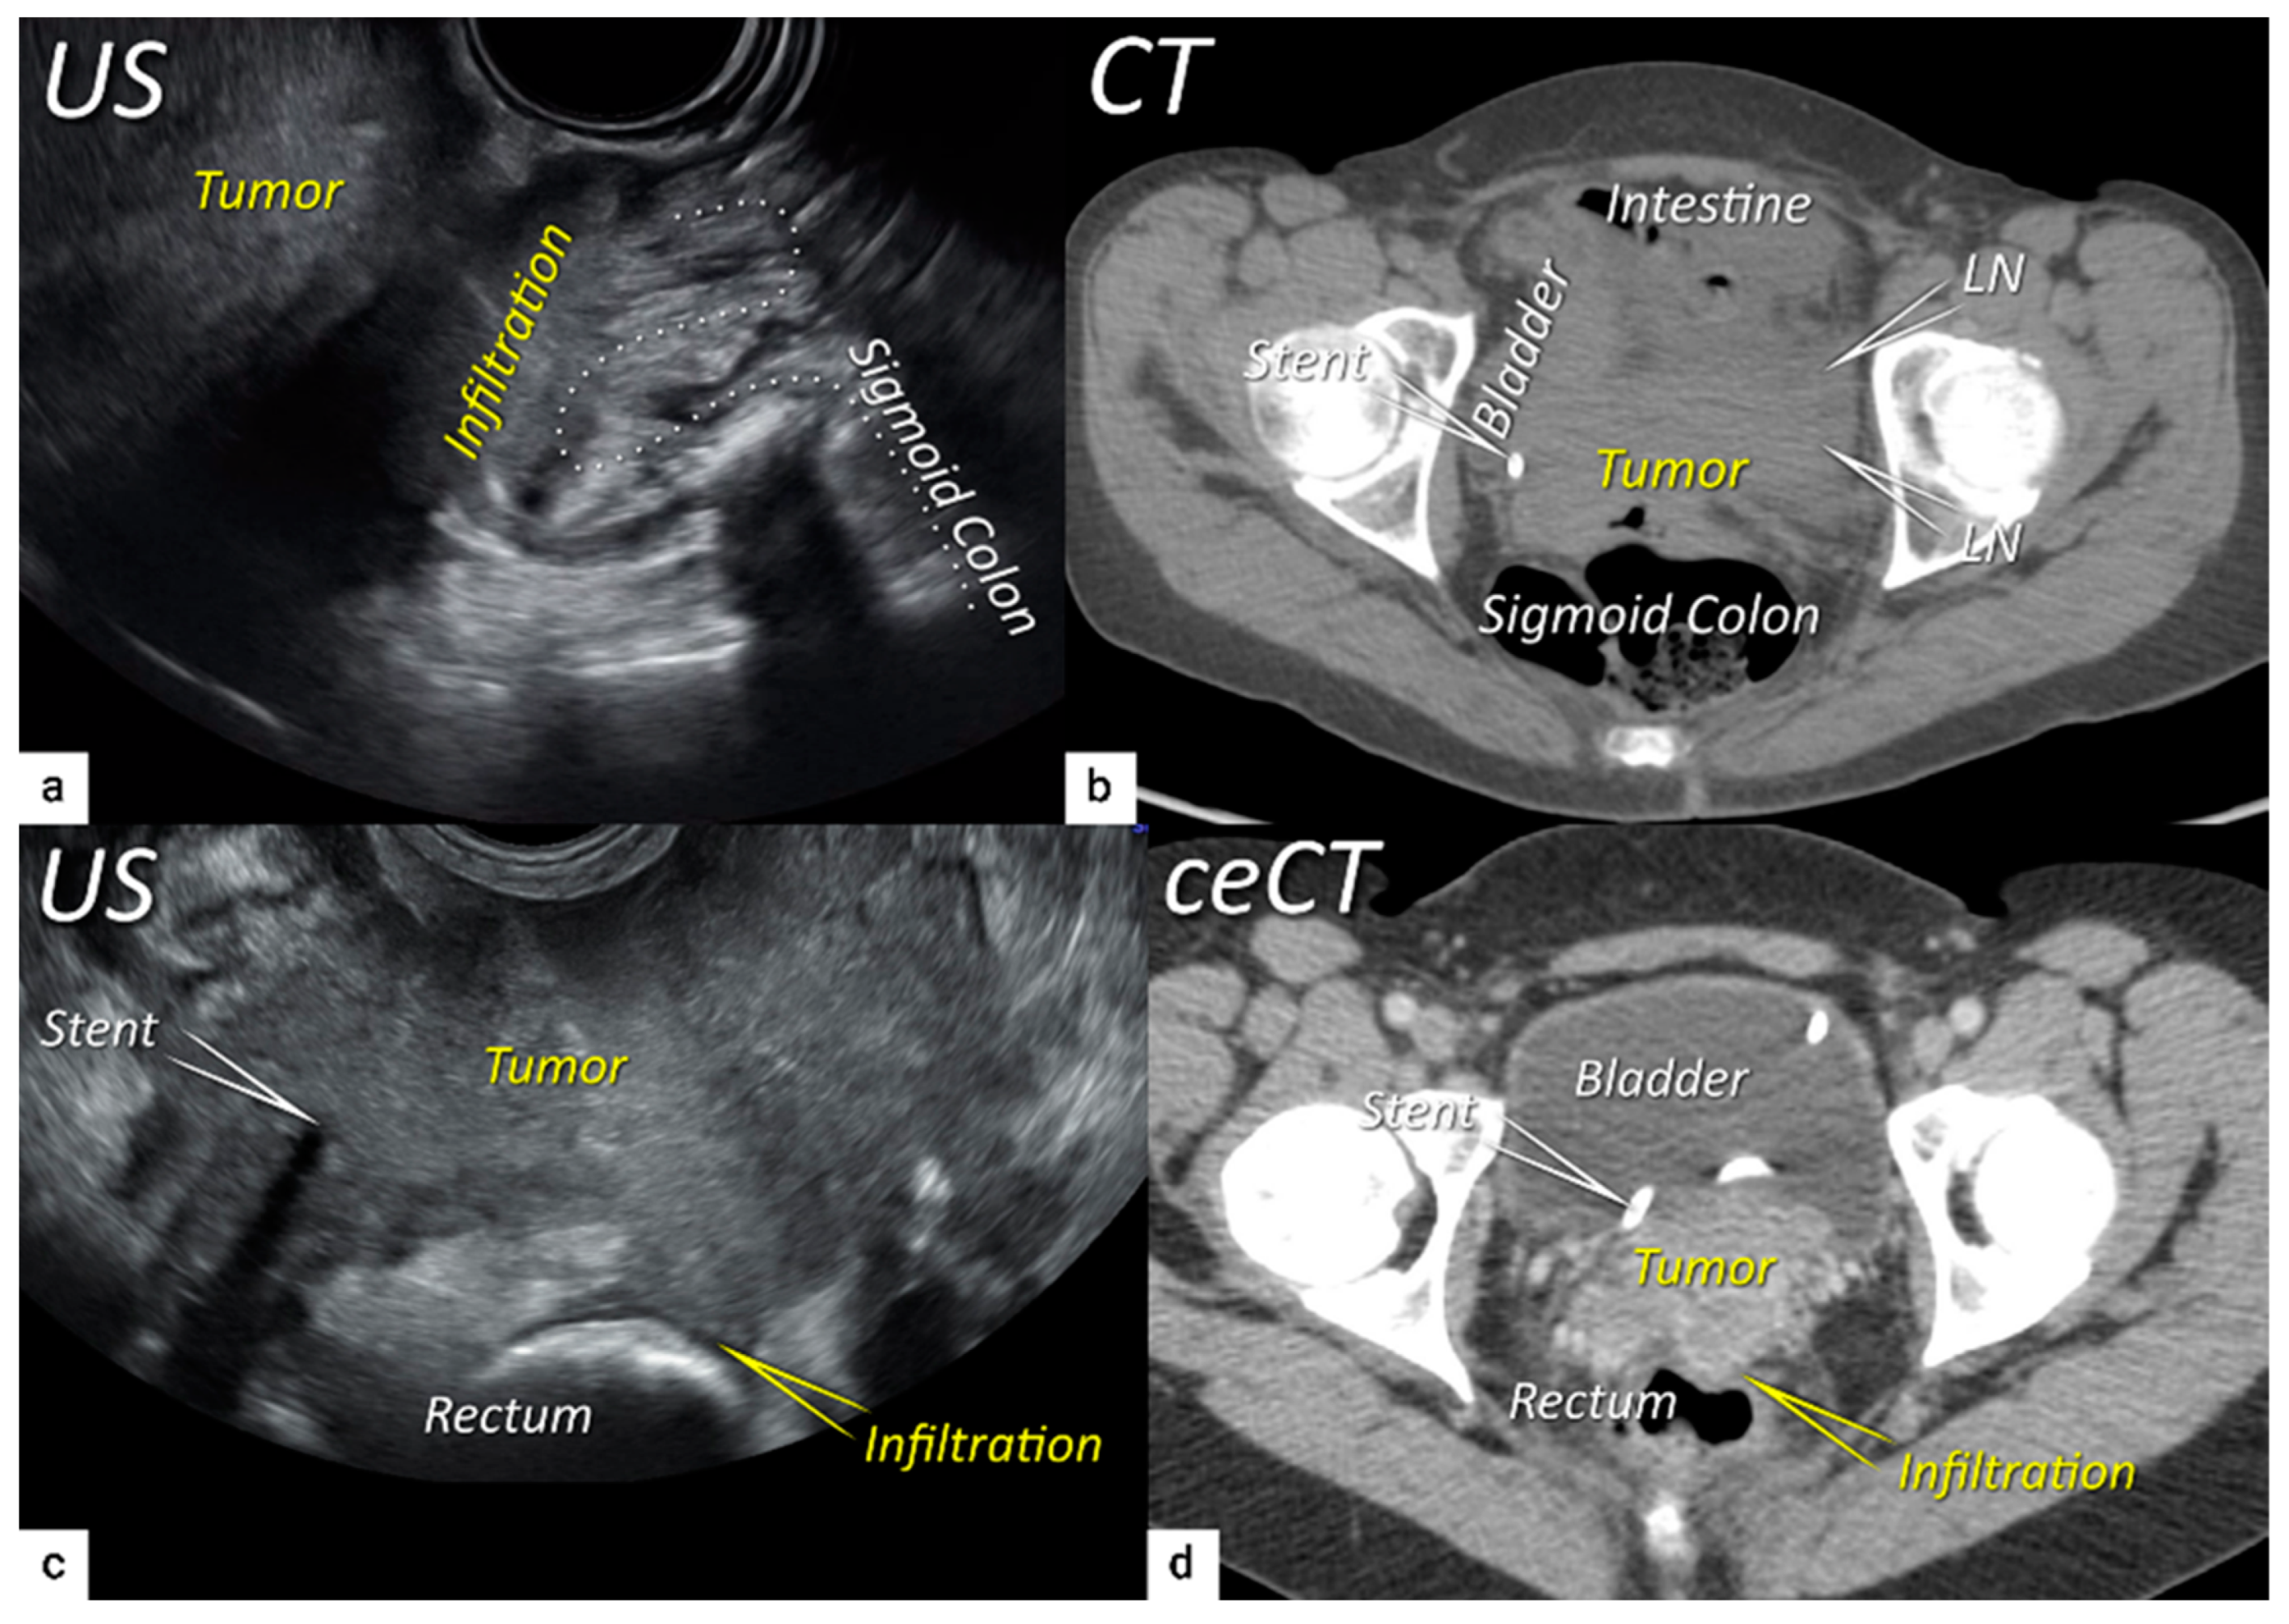

| T4f | IVAf | Tumour invasion into the mucosa of the bladder or rectum (biopsy-proven) or into adjacent organs. | US: Negative sliding sign, hypoechogenic tumour infiltration of bladder / rectal wall up to echogenic mucosa with polypoid tumor seen intraluminally. MRI: Focal or diffuse disruption of the normal T2-low signal intensity wall of the bladder/rectum, irregular or nodular wall, sometimes including an intraluminal tumour mass. Bulous edema sign, which is hyperintense thickening of the bladder mucosa on T2W images, is only an indirect sign of invasion and should not be regarded as T4 unless confirmed mucosal infiltration at cystoscopy. Infiltration of the posterior bladder wall without mucosal infiltration should not be regarded as T4a. |

3.4. Extension to surrounding organs (bladder, rectum, sigmoid colon)